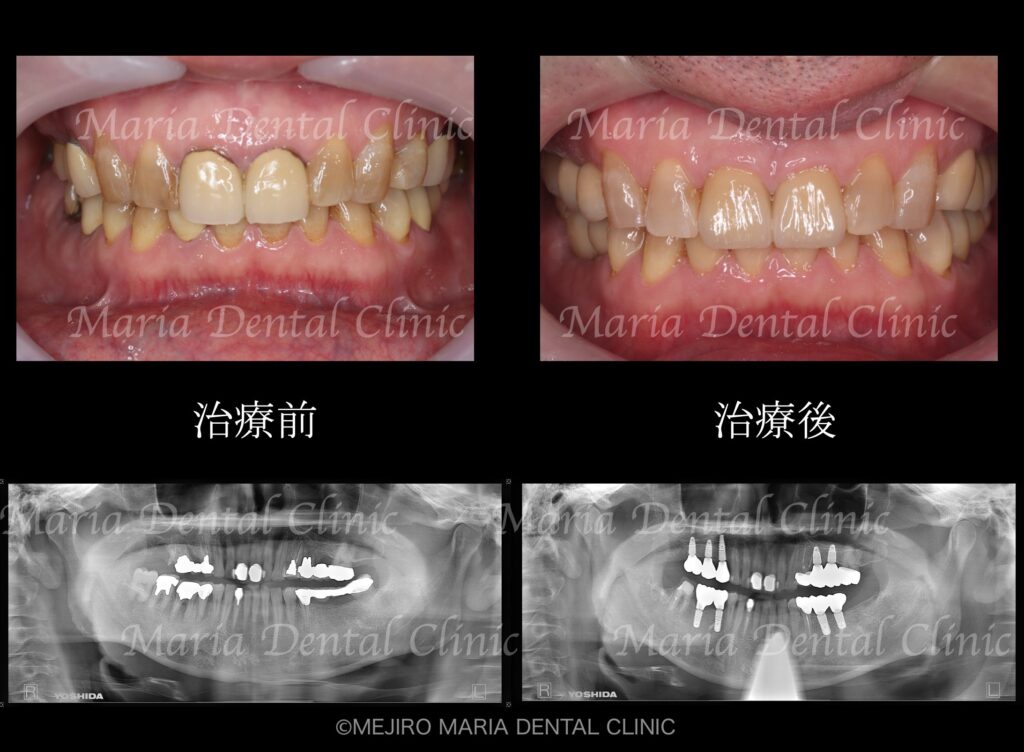

数年前より右上に咬合時の痛み(鋭く刺すような痛み)を感じるようになり、数件の歯科医院を受診するも原因の特定には至らず、経過を見るようにと言われていたとのことです。最後に通院した歯科医院にてクラックが発見されましたが、痛みは良くならず当院を受診されました。

初診時には右上7番に歯髄生活反応は確認できず、歯髄壊死が起因の根尖性歯周炎と診断しました。根管治療を開始するも、歯牙は既に破折しており患者様には抜歯することをおすすめさせていただきました。

患者様はインプラントを行うことには抵抗があり、抜歯後のプランに左上の親知らずを右上7番部位に移植することを選択されました。

精密根管治療終了後3ヶ月で、術前に確認できた病変の縮小は顕著に確認でき、予後経過は良好と判断します。今後、最終補綴処置に移行し経過観察を行っていきます。

今回は右上7番が歯根破折により、歯の保存が不可能なケースでした。

本症例では幸運なことに左上の親知らずが健在していたため、口腔外科医と歯内療法専門医との連携により歯牙移植を行うこととしました。

手術後、2週間で移植歯の生着を確認し、通法通りの精密根管治療を施したことで、根尖周囲組織に確認できた病変も3ヶ月後の経過観察では縮小を確認しました。